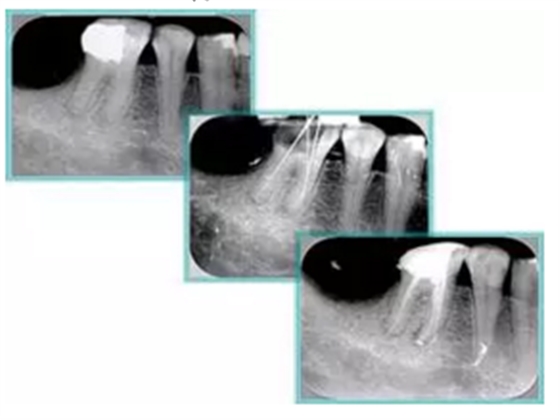

6. 術(shù)后 X 線片

術(shù)后 X 線片用來評定根管充填 長度、致密度(管壁清晰、側(cè)枝)等指標(biāo)。

圖為根管充填術(shù)后 X 線片。圖中可見,根管充填較好。右下圖有白色小點,為側(cè)方加壓導(dǎo)致糊劑擠出所致,表明根管充填比較致密。

致密、恰到好處的充填可去除干凈根管里感染灶,機體逐漸恢復(fù)。

多根牙時候需進(jìn)行偏移投照,正位投照無法說明具體哪根牙根管充填效果。